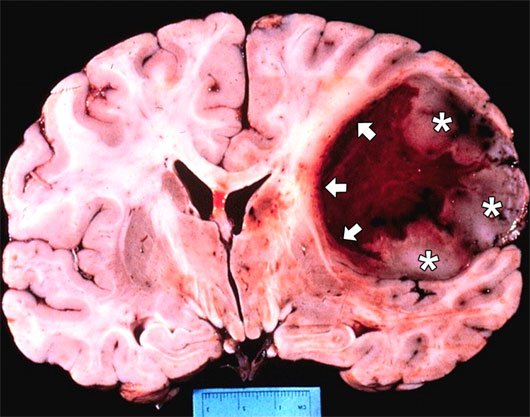

Ung thư não là một căn bệnh hiếm gặp nhưng có khả năng gây ảnh hưởng đến sức khỏe và tính mạng của người mắc phải. Các khối u ở não có thể xuất phát từ não (ung thư nguyên phát) hoặc di căn từ các bộ phận khác trong cơ thể (ung thư thứ phát). Vậy ung thư não ảnh hưởng như nào đến người bệnh? Dưới đây chúng tôi sẽ giải đáp chi tiết cho bạn hiểu hơn về bệnh ung thư não.

Triệu chứng ung thư não đặc trưng nhất bởi tình trạng tăng áp lực nội sọ do tăng thể tích của khối u, tăng thể tích do phù não và ứ đọng dịch não tủy. Ngoài ra còn có các triệu chứng mang tính chất định khu của khối u.

IV. Nguyên nhân gây ra ung thư não là gì?